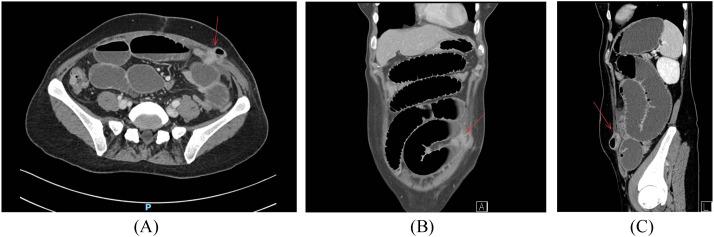

Port-site herniation (PSH) is a rare complication observed postlaparoscopic surgery, typically associated with port sizes of 10 mm or larger, commonly occurred at umbilicus. While occurrences of extra-umbilicus with port size smaller than 10 mm are rare, we present a case detailing a lateral 7 mm PSH diagnosed on the 8th day following a total laparoscopic hysterectomy. The patient exhibited clinical symptoms indicative of partial small bowel obstruction, which became apparent on the third postoperative day. Computed tomography revealed significant small bowel dilatation and herniation through the previously employed 7 mm trocar site. Notably, this trocar site had been utilized with uterine screw. Prompt laparoscopic repair successfully addressed the herniation. The patient demonstrated satisfactory recovery and was subsequently discharged. While current practice recommends fascial incision closure for port size ≥10 mm. In light of our case, we propose considering fascial closure for small-size trocar subjected to any use of a manipulator.

穿刺孔疝(PSH)是腹腔镜手术后观察到的一种罕见并发症,通常与10毫米或更大的穿刺孔尺寸有关,常见于脐部。虽然脐外穿刺孔尺寸小于10毫米的情况很少见,但我们报告一例详细病例,一名患者在全腹腔镜子宫切除术后第8天被诊断为外侧7毫米穿刺孔疝。患者表现出提示部分小肠梗阻的临床症状,术后第三天变得明显。计算机断层扫描显示小肠明显扩张,并通过先前使用的7毫米套管针穿刺孔发生疝出。值得注意的是,该套管针穿刺孔曾用于子宫螺钉。及时的腹腔镜修复成功解决了疝出问题。患者恢复良好,随后出院。虽然目前的做法建议对穿刺孔尺寸≥10毫米的情况进行筋膜切口闭合。鉴于我们的病例,我们建议考虑对使用过任何操作器械的小尺寸套管针进行筋膜闭合。